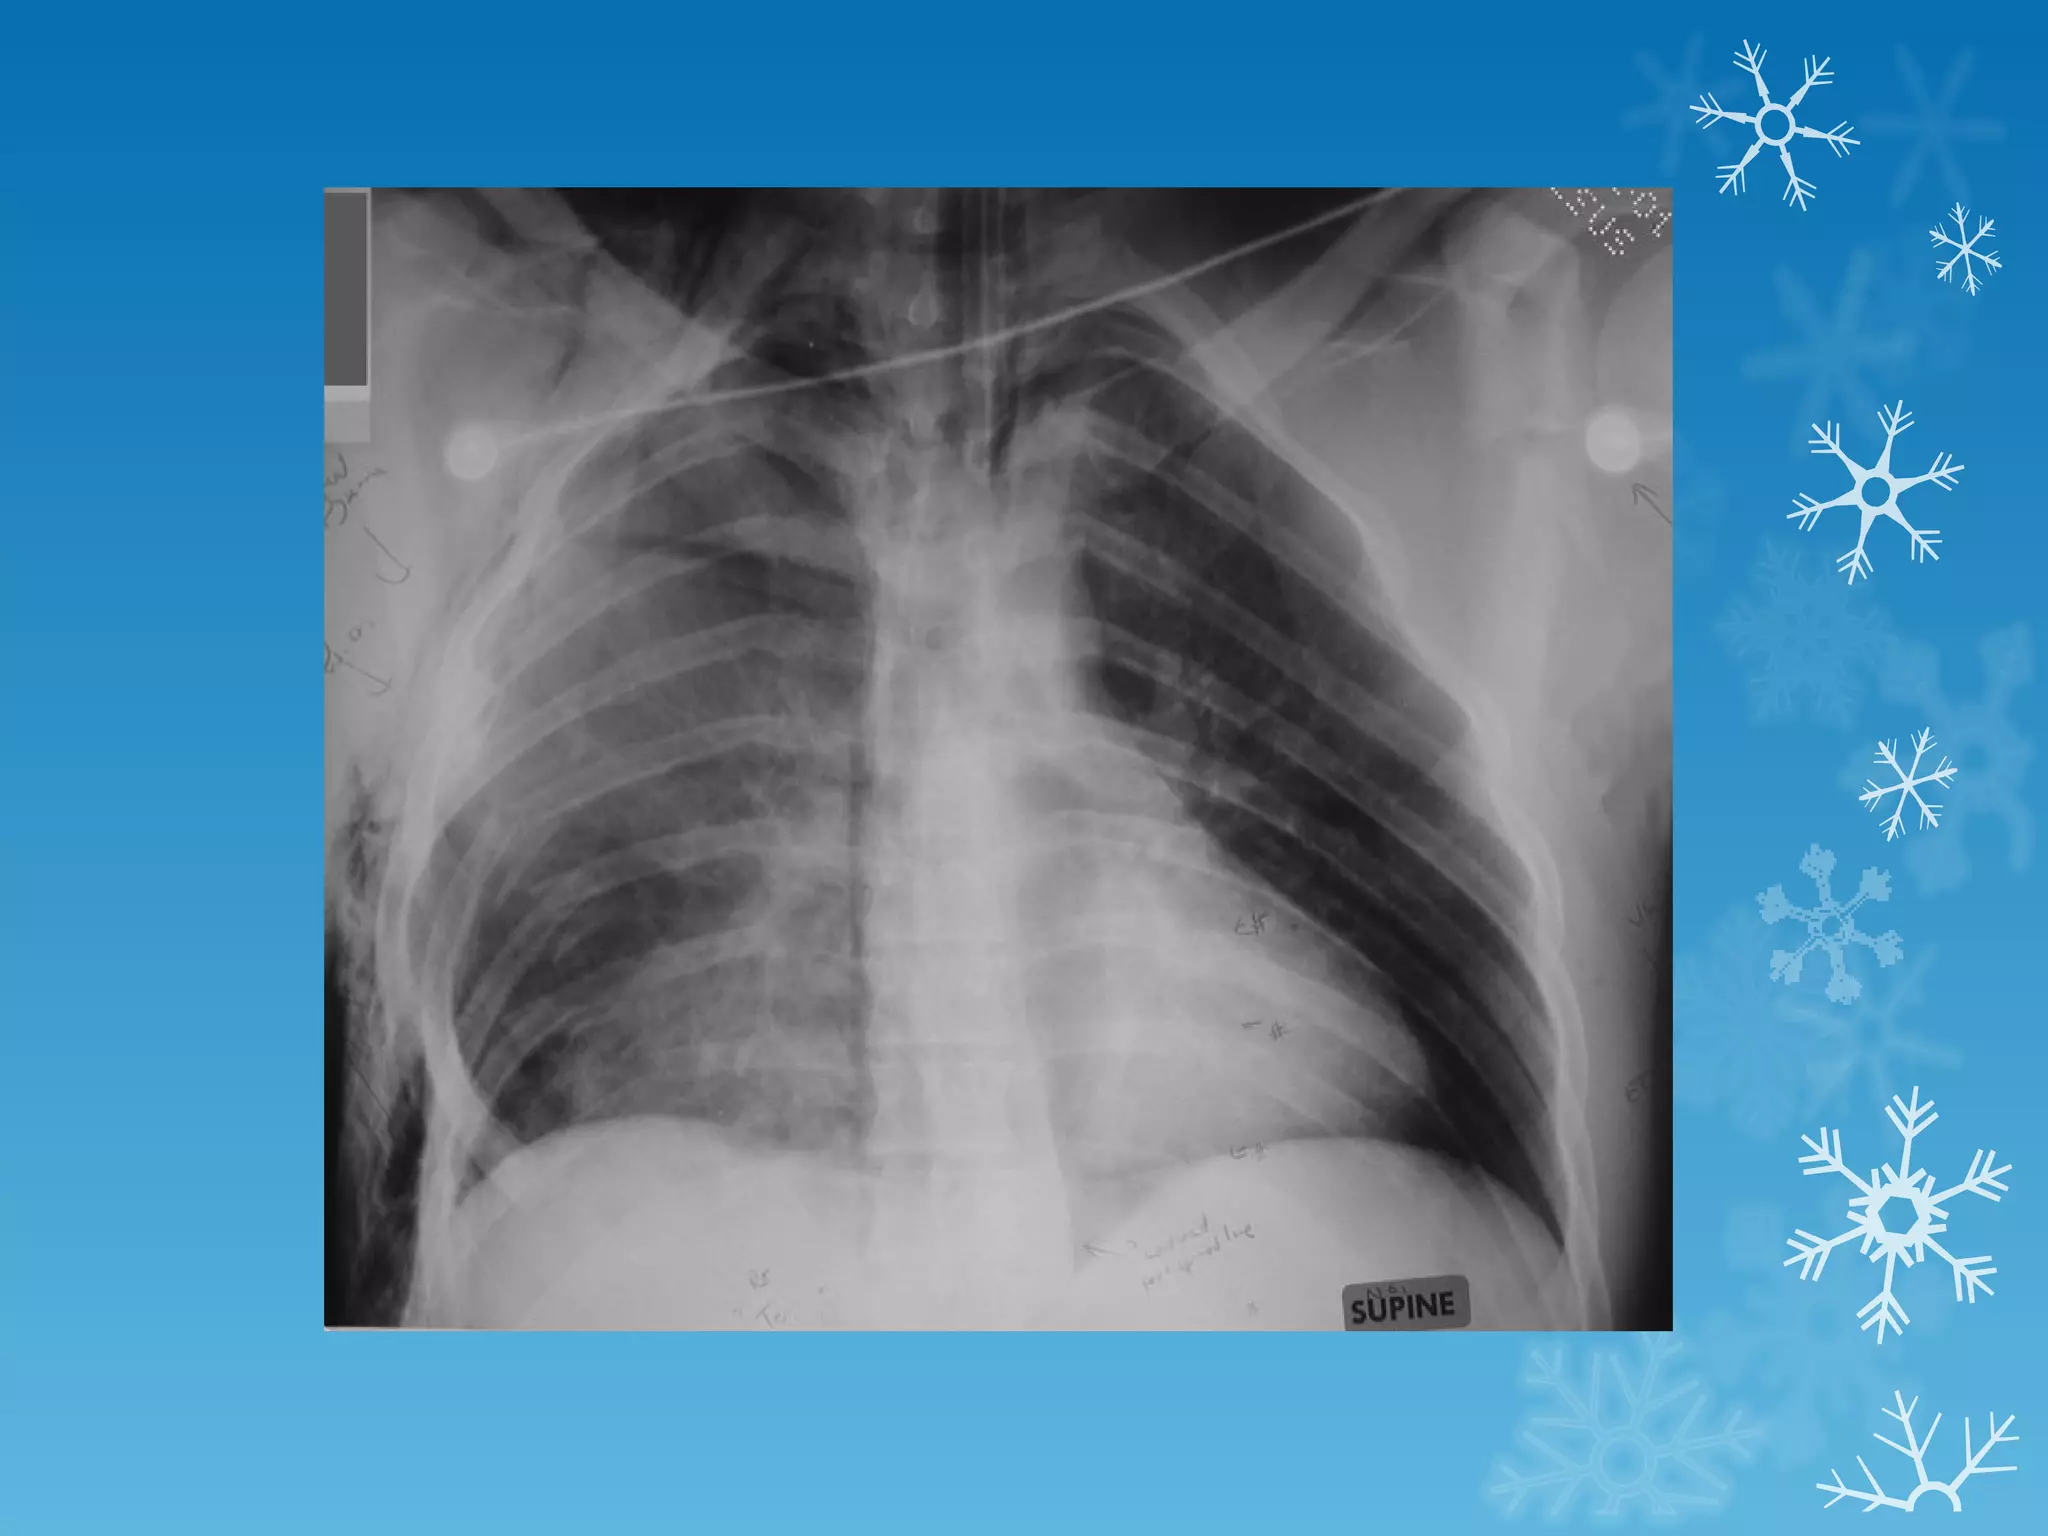

This document discusses chest x-ray interpretation and provides guidance on evaluating x-rays. It explains that tissue density determines how an x-ray beam penetrates, with denser tissues appearing whiter and less dense tissues appearing blacker. It also outlines different chest x-ray views and factors to consider like patient orientation, age, gender, and rotation. Abnormalities are described as appearing too white, too black, too large, or in the wrong place. The document stresses a systematic approach of identifying, localizing, describing lesions, and providing differential diagnoses.